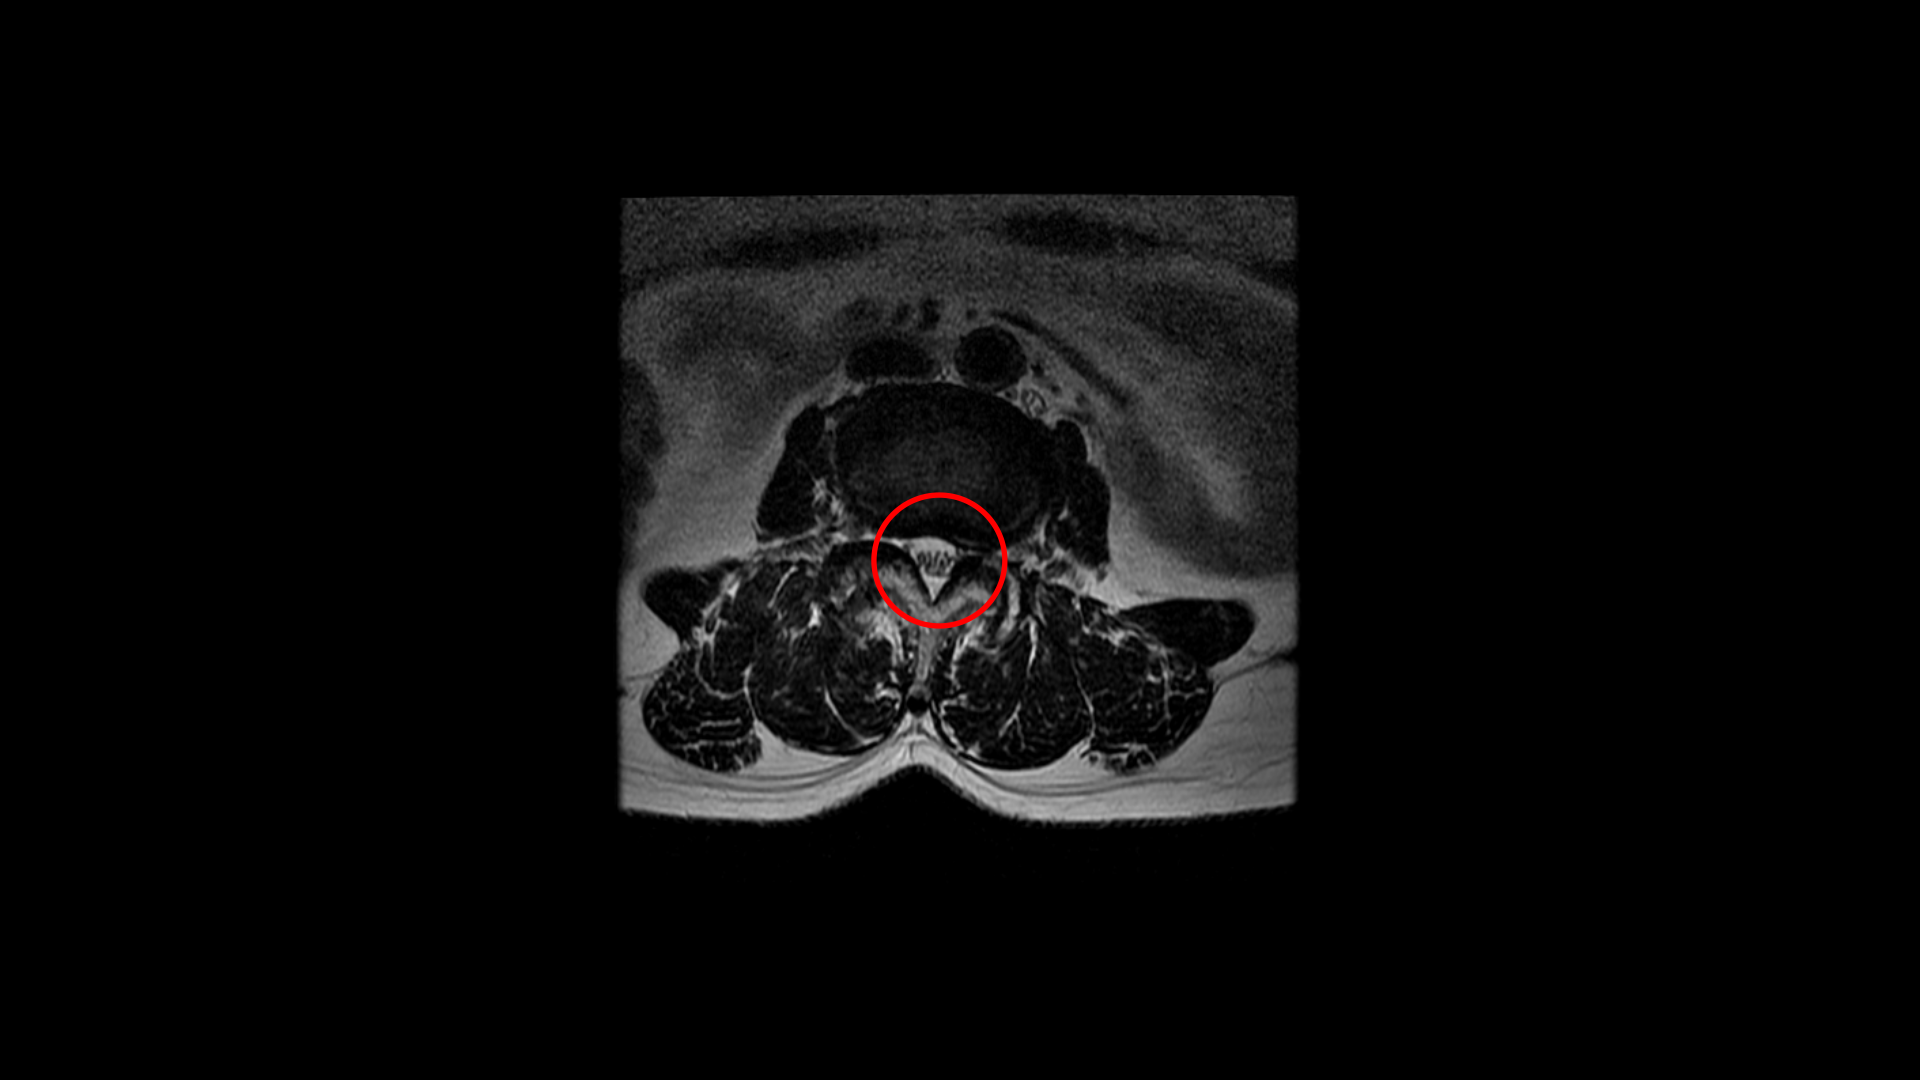

우선 이 환자분의 MRI를 함께 보겠습니다. 이 환자분의 척추에는 3번 4번과 4번 5번에 각각 1단계의 전방전위증이 있습니다.

그리고 4번 5번에도 왼쪽으로 퇴행성디스크와 후관절의 퇴행으로 신경 가지가 나가는 구멍이 좁아져 있습니다.

그리고 중심성 협착도 있습니다.

그런데 이 환자분의 제일 불편한 증상은 왼쪽이 아니고 오른쪽 엉치와 다리 증상입니다. 이분 오른쪽 신경 구멍들을 보면 전부 다 넓게 잘 열려 있습니다.

엉치와 다리 방사통을 일으킬만한 특별한 신경 눌림이 보이지 않는 것입니다. 그럼에도 불구하고 여러 마디의 전방전위증과 척추관 협착 그리고 디스크 탈출이 있으니까 그것을 원인으로 보고 신경 주사도 맞고 시술도 받으셨습니다. 그러나 별 효과는 없었습니다. 그리고 대학병원에서도 결국은 수술밖에 방법이 없다고 수술을 권유하였습니다.